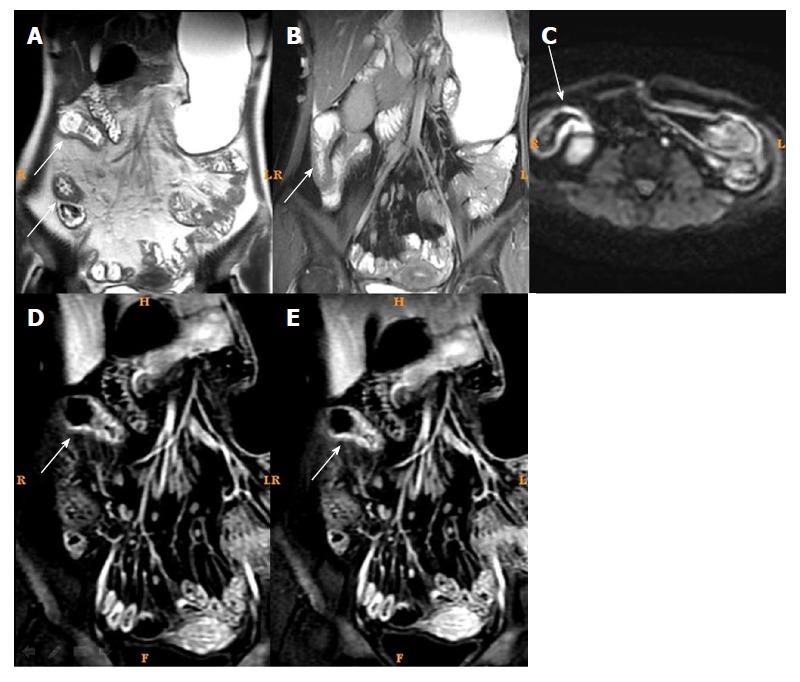

磁共振成像与克罗恩病内镜严重程度指数:相关性和一致性。

Magnetic resonance imaging and Crohn's disease endoscopic index of severity: Correlations and concordance.

To examine the correlation between magnetic resonance imaging (MRI) and endoscopic index of severity (CDEIS) in patients with Crohn's disease (CD).

METHODS

This was a retrospective study of 104 patients with CD that were treated at the Ruijin Hospital between March 2015 and May 2016. Among them, 61 patients with active CD were evaluated before/after treatment. MRI and endoscopy were performed within 7 d. CDEIS was evaluated. MRI parameters included MaRIA scores, total relative contrast enhancement (tRCE), arterial RCE (aRCE), portal RCE (pRCE), delay phase RCE (dRCE), and apparent diffusion coefficient. The correlation and concordance between multiple MRI findings and CDEIS changes before and after CD treatment were examined.

RESULTS

Among the 104 patients, 61 patients were classified as active CD and 43 patients as inactive CD. Gender, age, disease duration, and disease location were not significantly different between the two groups (all > 0.05). CRP levels were higher in the active group than in the inactive group (25.12 ± 4.12 5.14 ± 0.98 mg/L, < 0.001). Before treatment, the correlations between CDEIS and MaRIAs in all patients were = 0.772 for tRCE, = 0.754 for aRCE, = 0.738 for pRCE, and = 0.712 for dRCE (all MaRIAs, < 0.001), followed by MRI single indexes. Among the active CD patients, 44 cases were remitted to inactive CD after treatment. The correlations between CDEIS and MaRIAs were = 0.712 for aRCE, = 0.705 for tRCE, = 0.685 for pRCE, and = 0.634 for dRCE (all MaRIAs, < 0.001).

CONCLUSION

Arterial MaRIA should be an indicator for CD follow-up and dynamic assessment. CD treatment assessment was not completely concordant between CDEIS and MRI.